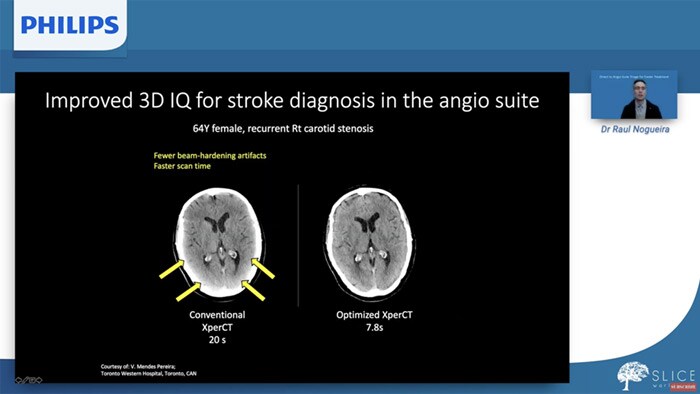

Dr. Vitor Mendes Pereira explains how 3D imaging in the angio suite influences faster treatment of ELVOs.

This symposium session took place during the LINNC Paris, 2021.

‘Significant advances in technology mean that we are now able to identify, plan and treat ischemic stroke patients in the angiography suite, without the need for a separate CT or MR scan.’

Dr Raul Nogueira (Grady Memorial Hospital, Atlanta), LINNC 2019